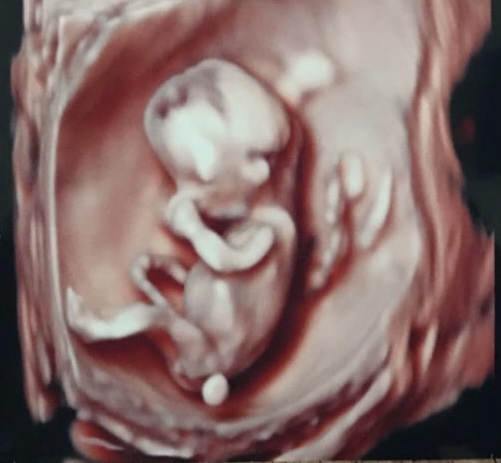

Holky, tak já jdu na utz nakonec už zítra, doktorka mě předobjednala 🙂 budu 7+6 podle ms, tak snad to nebude moc brzo...

@jade85 tak zítra držím palce. Určitě bude všechno v pořádku 🍀 🍀

Jinak jsem vlastně ráda, že ultrazvuk bude až v pátek. Holky, co myslíte, je možné už takhle brzo udělat utz přes břicho? Chtěla bych pokud možno těhotenství úplně bez vaginálních vyšetření. Max stěr na streptokoka před porodem. Určitě to budu řešit s doktorkou, ale zas se jí nechci ptát na úplnou blbost....